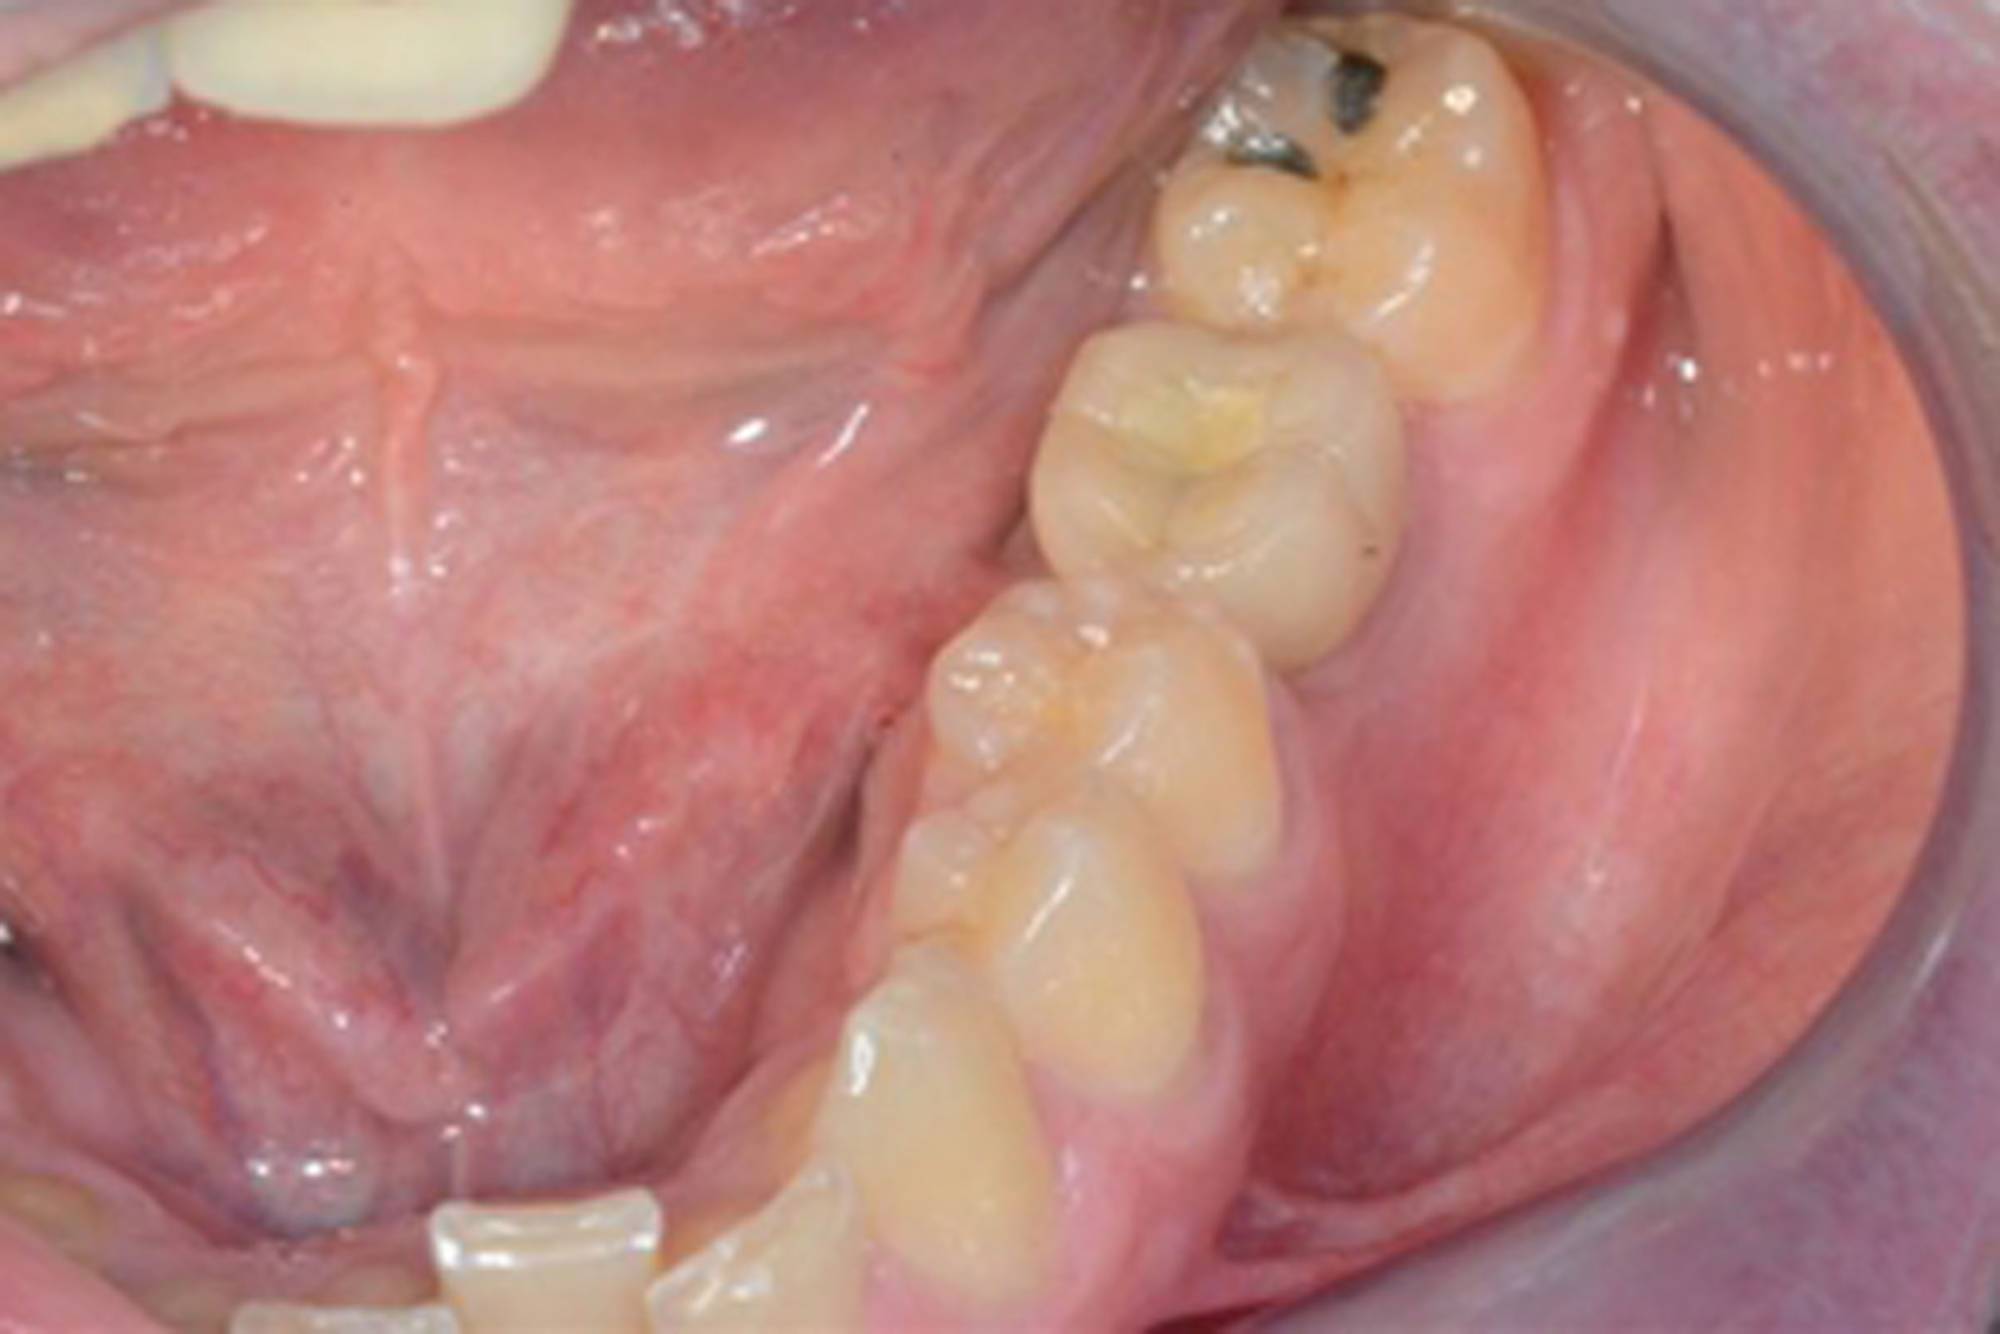

L'impianto dentale osteointegrato è una sorta di radice artificiale che si inserisce nell’osso del paziente, per rimpiazzare un dente mancante.

L'impianto, oltre a essere un metodo sicuro, garantisce l'aspetto esteriore e la piena funzionalità di un dente naturale. Oltre a ciò, mantiene l’integrità dell’osso, non va ad intaccare i denti adiacenti - come invece farebbe un ponte - e migliora l’estetica facciale prevenendo la perdita ossea.

Gli impianti sono molto versatili e possono essere usati per sostituire un dente singolo, più denti fissi o addirittura un'intera arcata. Inoltre, possono essere inseriti sotto una protesi mobile per stabilizzarla migliorandone il comfort.